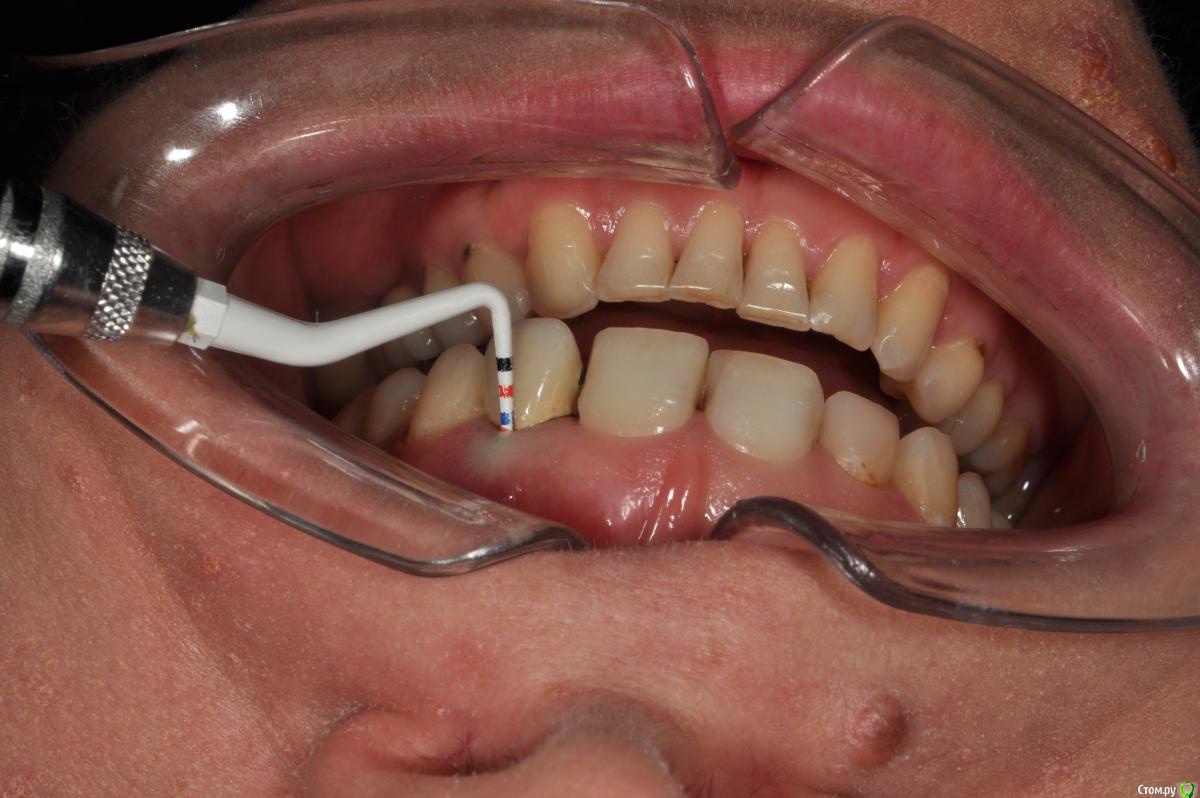

Пациентка 37 лет, не курит, соматически здорова. Частое выпадение ЛШКВ с коронкой. Диагностирована  фрактура вестибулярной стенки кореня зуба 22. Линия улыбки высокая. Биотип толстый.  Отсутствие вестибулярной пластинки, карман 8мм без ексудата.  Латеротрузия через 22.